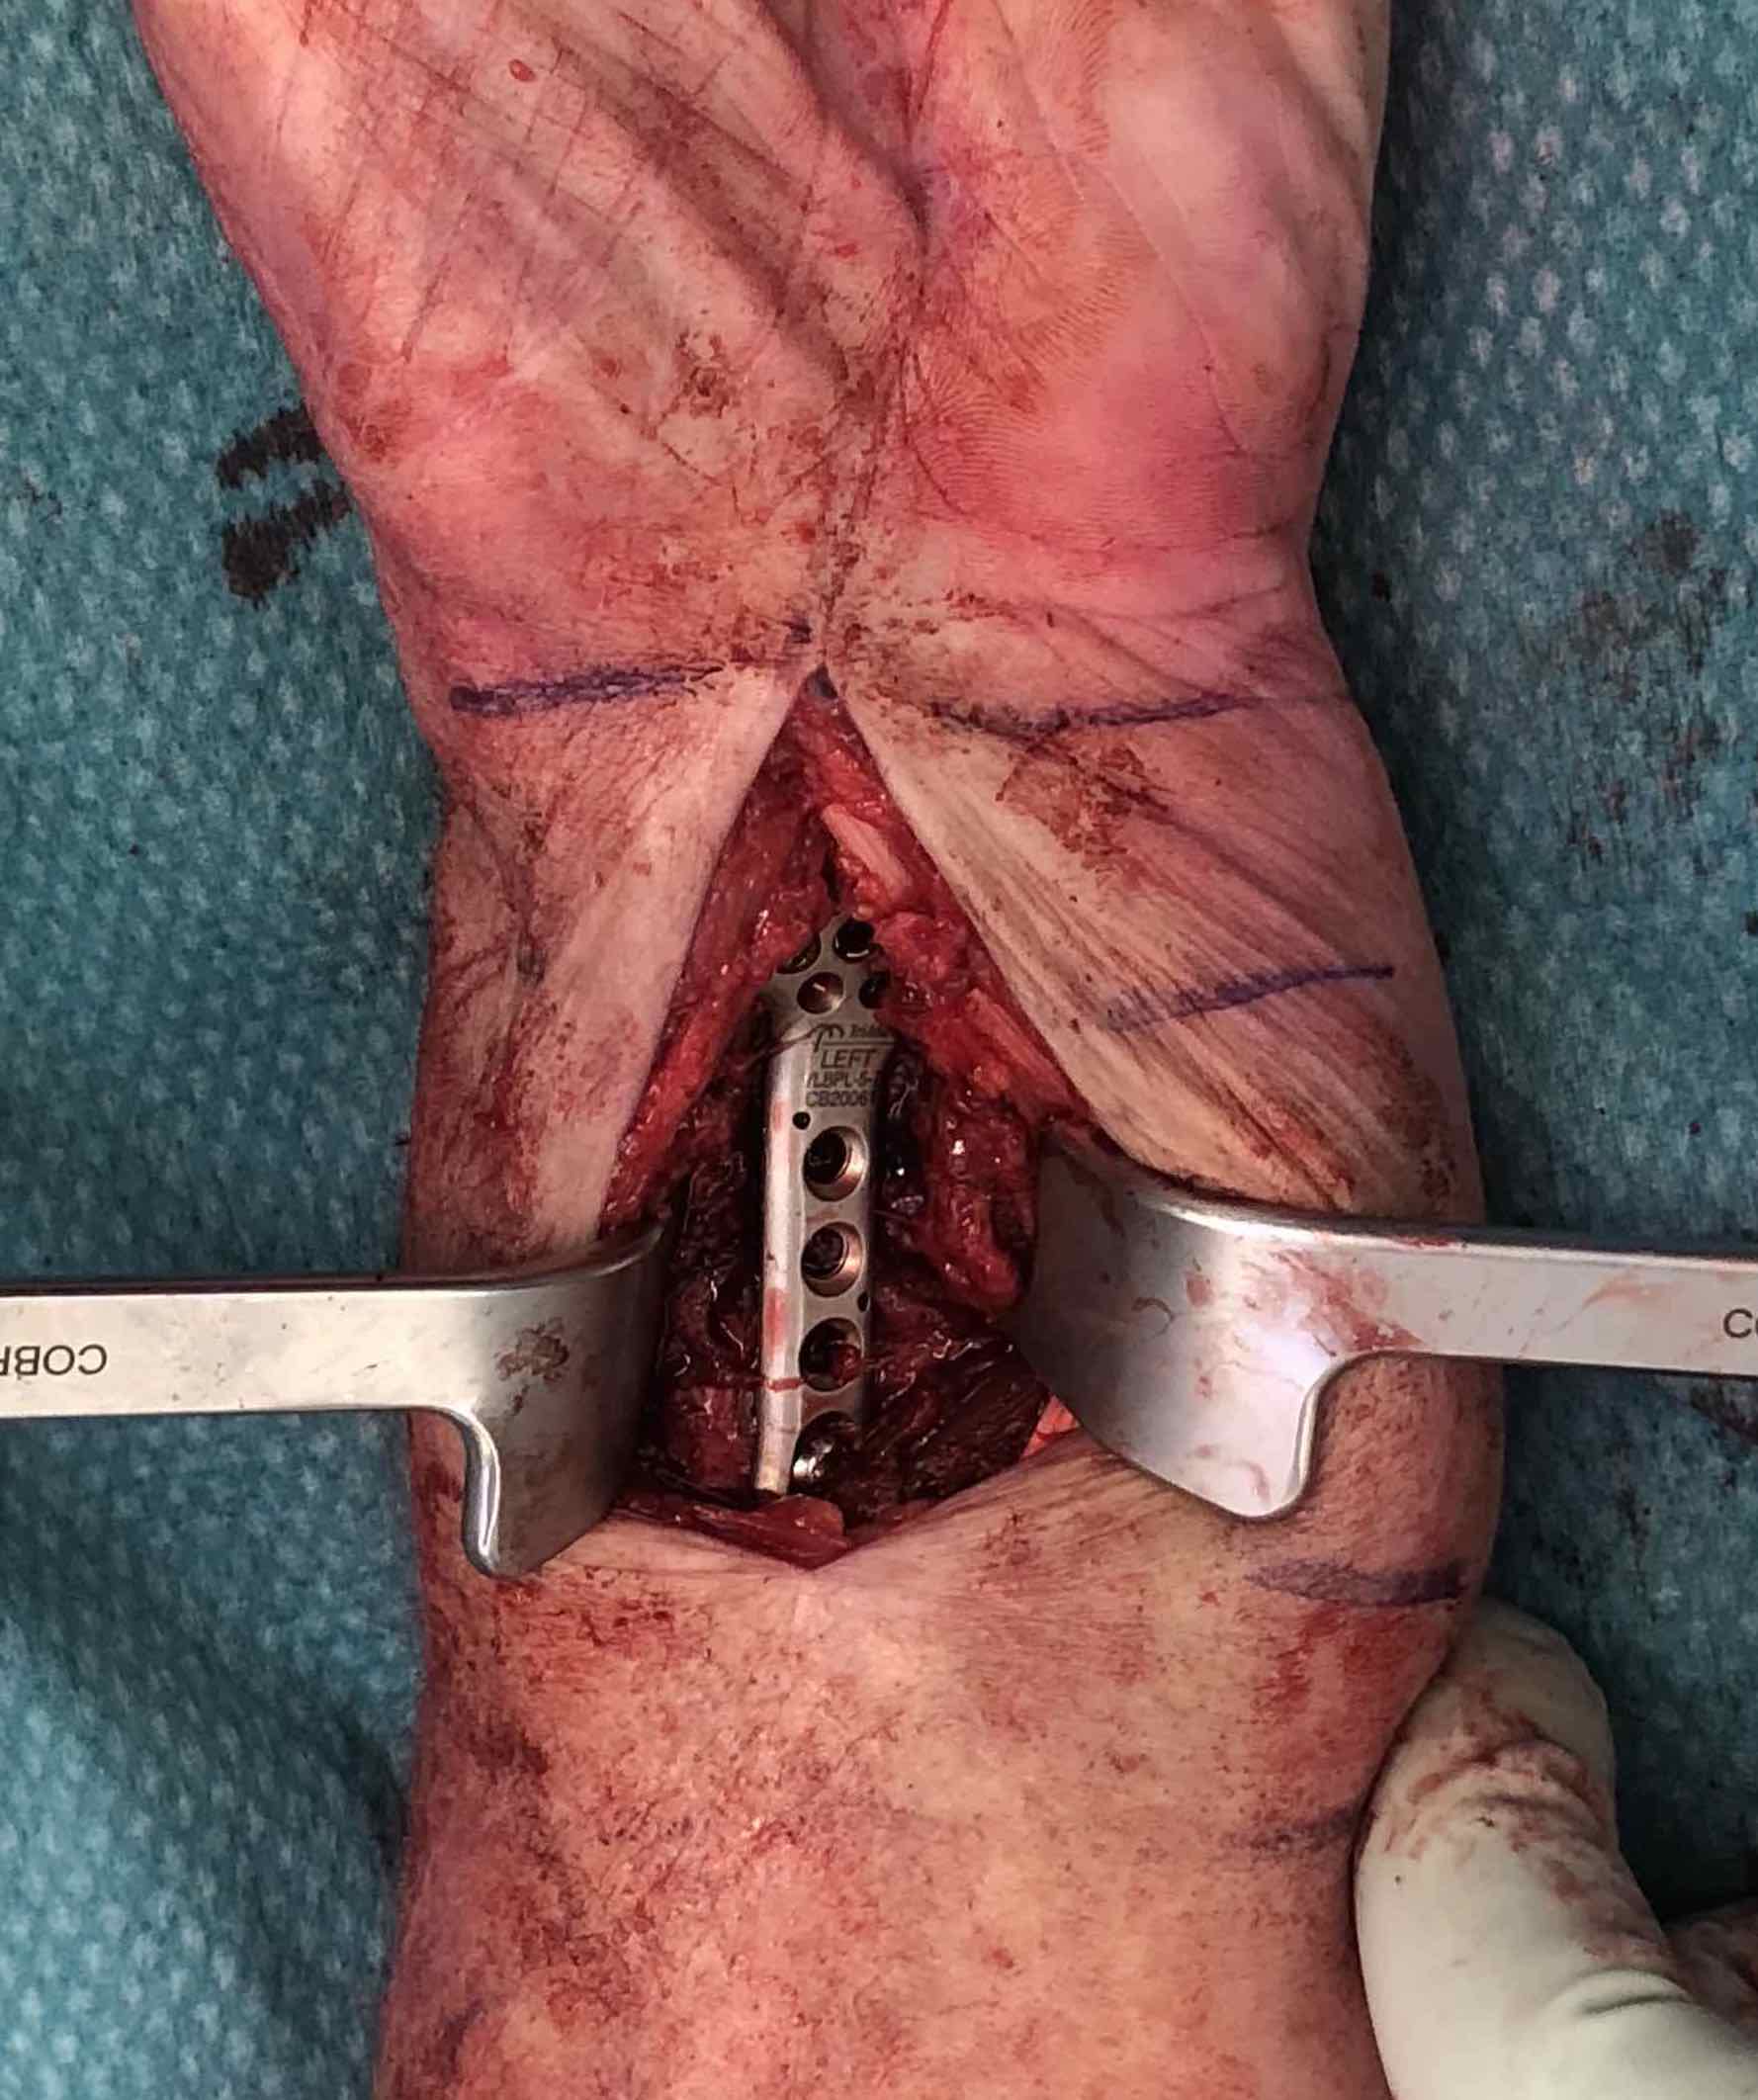

Volar locking plate technique

AO surgery modified Henry to distal forearm

Vumedi volar locking plate distal radius

Bed of FCR approach

- incision over FCR and mobilize ulnarly

- divide fascia in bed of FCR and retract radial artery laterally

- L shaped released of pronator quadratus

- cannot make volar capsulotomy - divides radiocarpal ligaments and causes instability

- elevate 1st extensor compartment (APL / EPB)

- release brachioradialis from radial styloid

Reduce fragments and temporarily stabilize with K wires

- apply volar plate with screw fixation in scaphoid and lunate fragments

- ensure not beyond watershed line to avoid flexor tendon irritation / rupture

- engage dorsal cortex but not too long to prevent EPL rupture

- on lateral, raise hand 30o to view joint

- +/- radial styloid plate if required